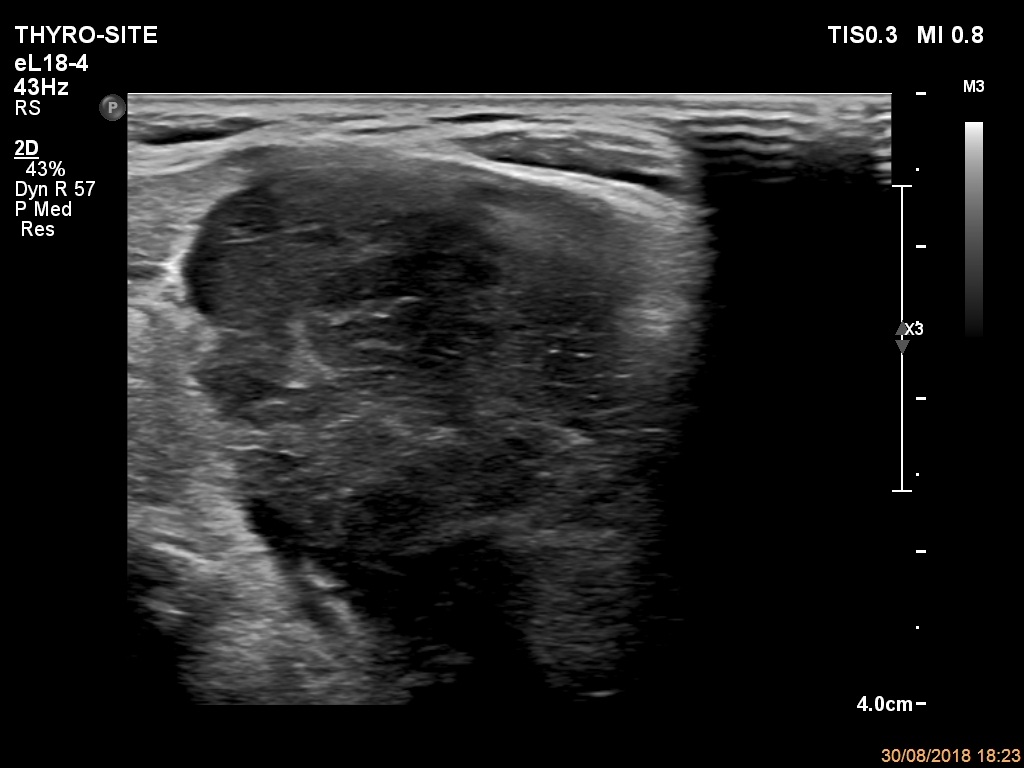

Ultrasonography. The thyroid was echonormal. There were a few hypoechogenic areas in the right lobe. There was a hypoechogenic mass with irregular shape in the left lobe. The lesion had echonormal fields and connective tissue. The microflow imaging revealed no intranodular vascularization while the lesion proved to be very hard on elastography.